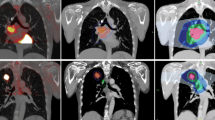

The planning CT was done with the patient in the standard supine position with lung board and kneefix immobilisation. Reference set-up marks were tattooed at CT. The planning PET/CT was the same position, with patient aligned to tattoos using lasers. Safety checks were essential from a radiation protection perspective and were performed to ensure that the PET/CT scan could be acquired prior to injecting the patient. The possibility of the patient colliding with the gantry was checked and eliminated, and the patient’s ability to tolerate the enclosed scanner was confirmed. The patient was then injected with FDG. The PET/CT scan (the hot session) was acquired 1 h after the injection. The radiation therapists were responsible for establishing the patient into the correct treatment position and for the acquisition of the CT scan. The diagnostic radiographers were responsible for the PET capture. All contouring was done on Advantage Sim Workstation.

The GTV was delineated twice. Firstly, this was done with conventional planning CT scan alone (CT-GTV) without reference to the PET-CT. The GTV was restricted to the visible primary tumour defined on diagnostic CT scan and bronchoscopy, and to any mediastinal node enlarged (> 1 cm diameter) on diagnostic CT scan and/or proven histologically involved on mediastinoscopy. A second GTV (PET-GTV) was drawn using fused PET-CT and planning CT images. Similarly, GTV was defined as the visible primary tumour, defined on diagnostic CT scan and bronchoscopy which is visible on the fused PET-CT images, and nodes considered as involved on a standard PET-CT scan and/or proven histologically involved on mediastinoscopy. An uptake threshold of 35% was applied to avoid any possible exclusion of active disease.

Separate plans based on the CT and PET/CT volumes were generated. The minimum prescribed dose of radiation was 60 Gy at 2 Gy per fraction. Ninety-five percent of the dose covered 100% of the PTV for both CT and PET/CT plans. The patient was subsequently treated using the PET/CT plan.